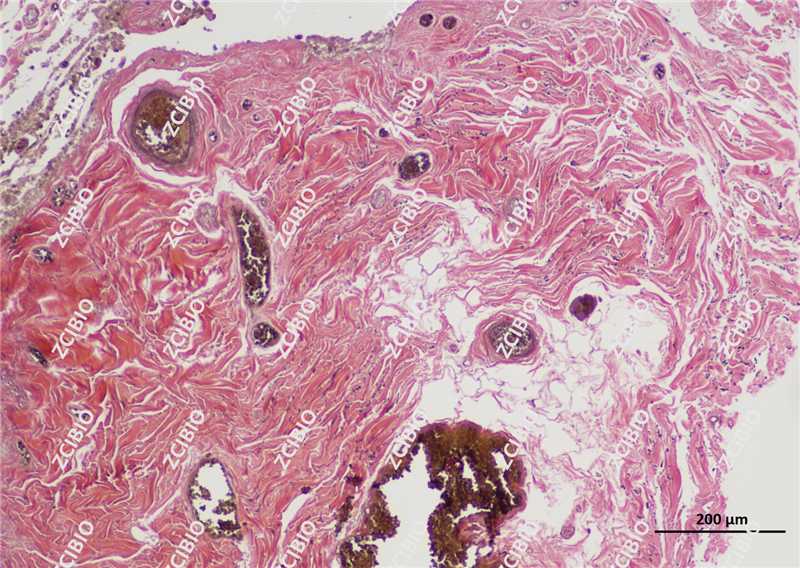

弹力纤维紫红色,胶原纤维红色,背景其他成分黄色

实验结果展示: